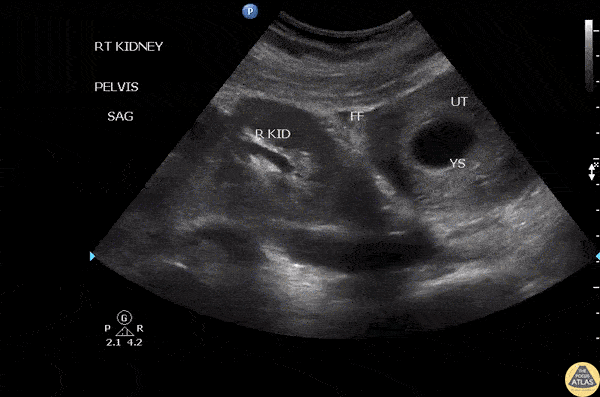

Renal/GU - Pelvic Kidney

A G1P0 female presented to the ED with vaginal bleeding, abdominal pain, and stable vital signs. Examination reveals a mass palpable supero-lateral to the uterus on the right. Ultrasound revealed a pelvic kidney. Image courtesy of Robert Jones DO, FACEP @RJonesSonoEM Director, Emergency Ultrasound; MetroHealth Medical Center; Professor, Case Western Reserve Medical School, Cleveland, OH View his original post here